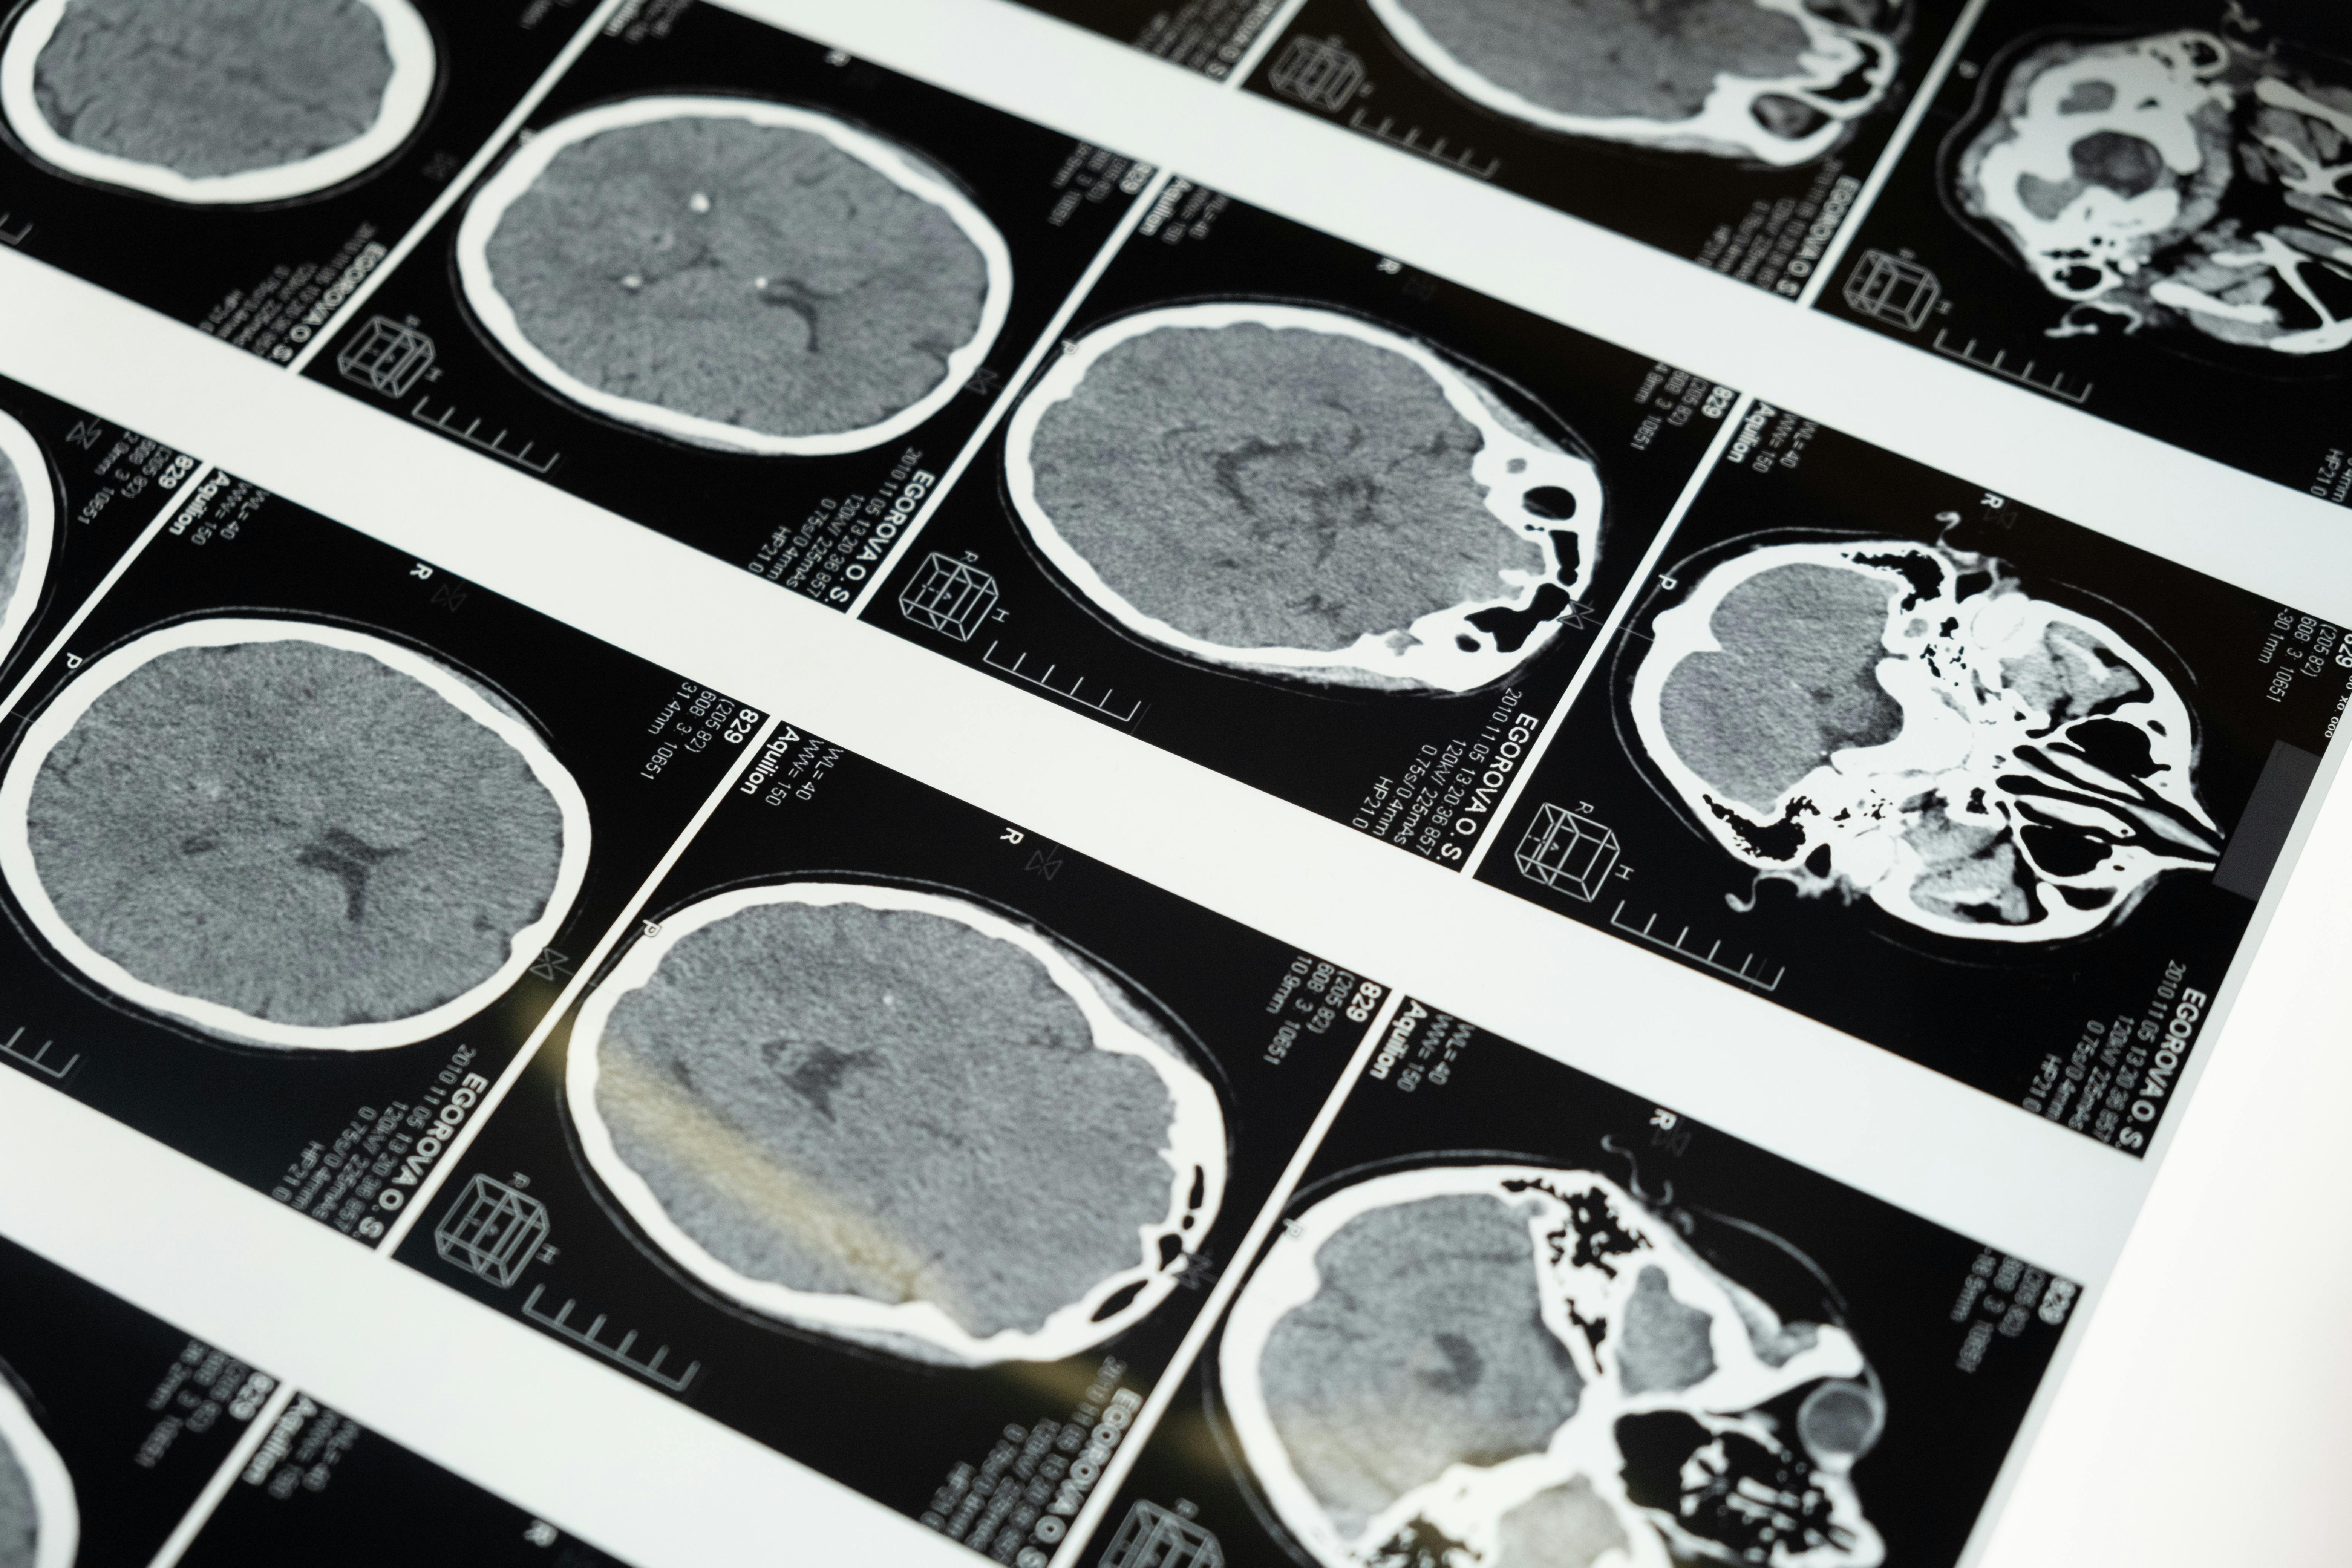

언어장애는 고혈압에 의해 뇌졸중이 시작되었음을 암시하는 또 하나의 주요 신호입니다. 뇌의 브로카 영역(말하는 기능)이나 베르니케 영역(이해하는 기능)에 혈류가 일시적으로 차단될 경우, 말이 어눌해지거나 상대방의 말을 잘 이해하지 못하는 증상이 갑자기 나타날 수 있습니다. 고혈압성 뇌졸중 초기에는 다음과 같은 증상이 자주 보고됩니다: - 평소처럼 말하려고 했지만 단어가 잘 떠오르지 않음 - 말이 엉키거나 단어 순서가 이상함 - 대화 상대의 말이 갑자기 이해되지 않음 - 말을 하려는데 발음이 뭉개지고, 침이 샐 정도로 입 근육이 무력해짐 이러한 증상은 단 몇 분간 나타났다가 사라질 수 있으나, 이는 일과성 허혈 발작(TIA)일 수 있으며, 48시간 이내에 본격적인 뇌졸중으로 발전할 확률이 매우 높습니다. 특히 고혈압이 있는 사람은 이러한 경고 신호를 단순한 피로나 스트레스로 넘기지 말고, 즉시 병원에서 CT나 MRI 등의 정밀 검사를 받아야 합니다. 언어장애는 의사소통의 어려움을 넘어 뇌 기능의 심각한 손상을 암시하므로, 초기 대응 속도가 생명을 좌우하게 됩니다. 갑자기 말이 어눌하거나 이상하다고 느껴진다면 즉시 주변에 도움을 요청하고 병원으로 향해야 합니다.